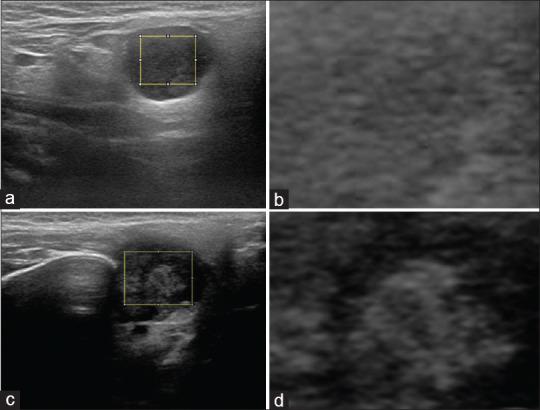

From August 2007 to May 2018, 144 adult patients who had major salivary gland tumors and subsequently underwent surgery were recruited for this study. Representative brightness mode US pictures were selected for texture analysis and used to develop a prediction model.

We found that the grayscale intensity and standard deviation of the intensity were significantly different between malignant and pleomorphic adenomas. The contrast, inverse difference (INV) movement, entropy, dissimilarity, and INV also differed significantly between benign and malignant tumors. We used stepwise selection of predictors to develop an objective predictive model, as follows: Score = 1.138 × Age - 1.814 × Intensity + 1.416 × Entropy + 1.714 × Contrast. With an optimal cutoff of 0.58, the diagnostic performance of this model had a sensitivity, specificity, overall accuracy, and area under the curve of 83% (95% confidence interval [CI]: 74%-92%), 74% (65%-84%), 78% (72%-85%), and 0.86 (0.80-0.92), respectively.